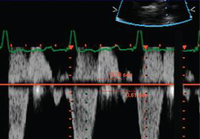

Doppler em um paciente com regurgitação pulmonar após reparo de tetralogia de Fallot. O paciente tem ventrículo direito não restritivo e onda "A" não é observada no espectro do Doppler de artéria pulmonar

De: Chaturvedi RR, Redington AN. Heart. 2007 Jul;93(7):880-9; usado com permissão